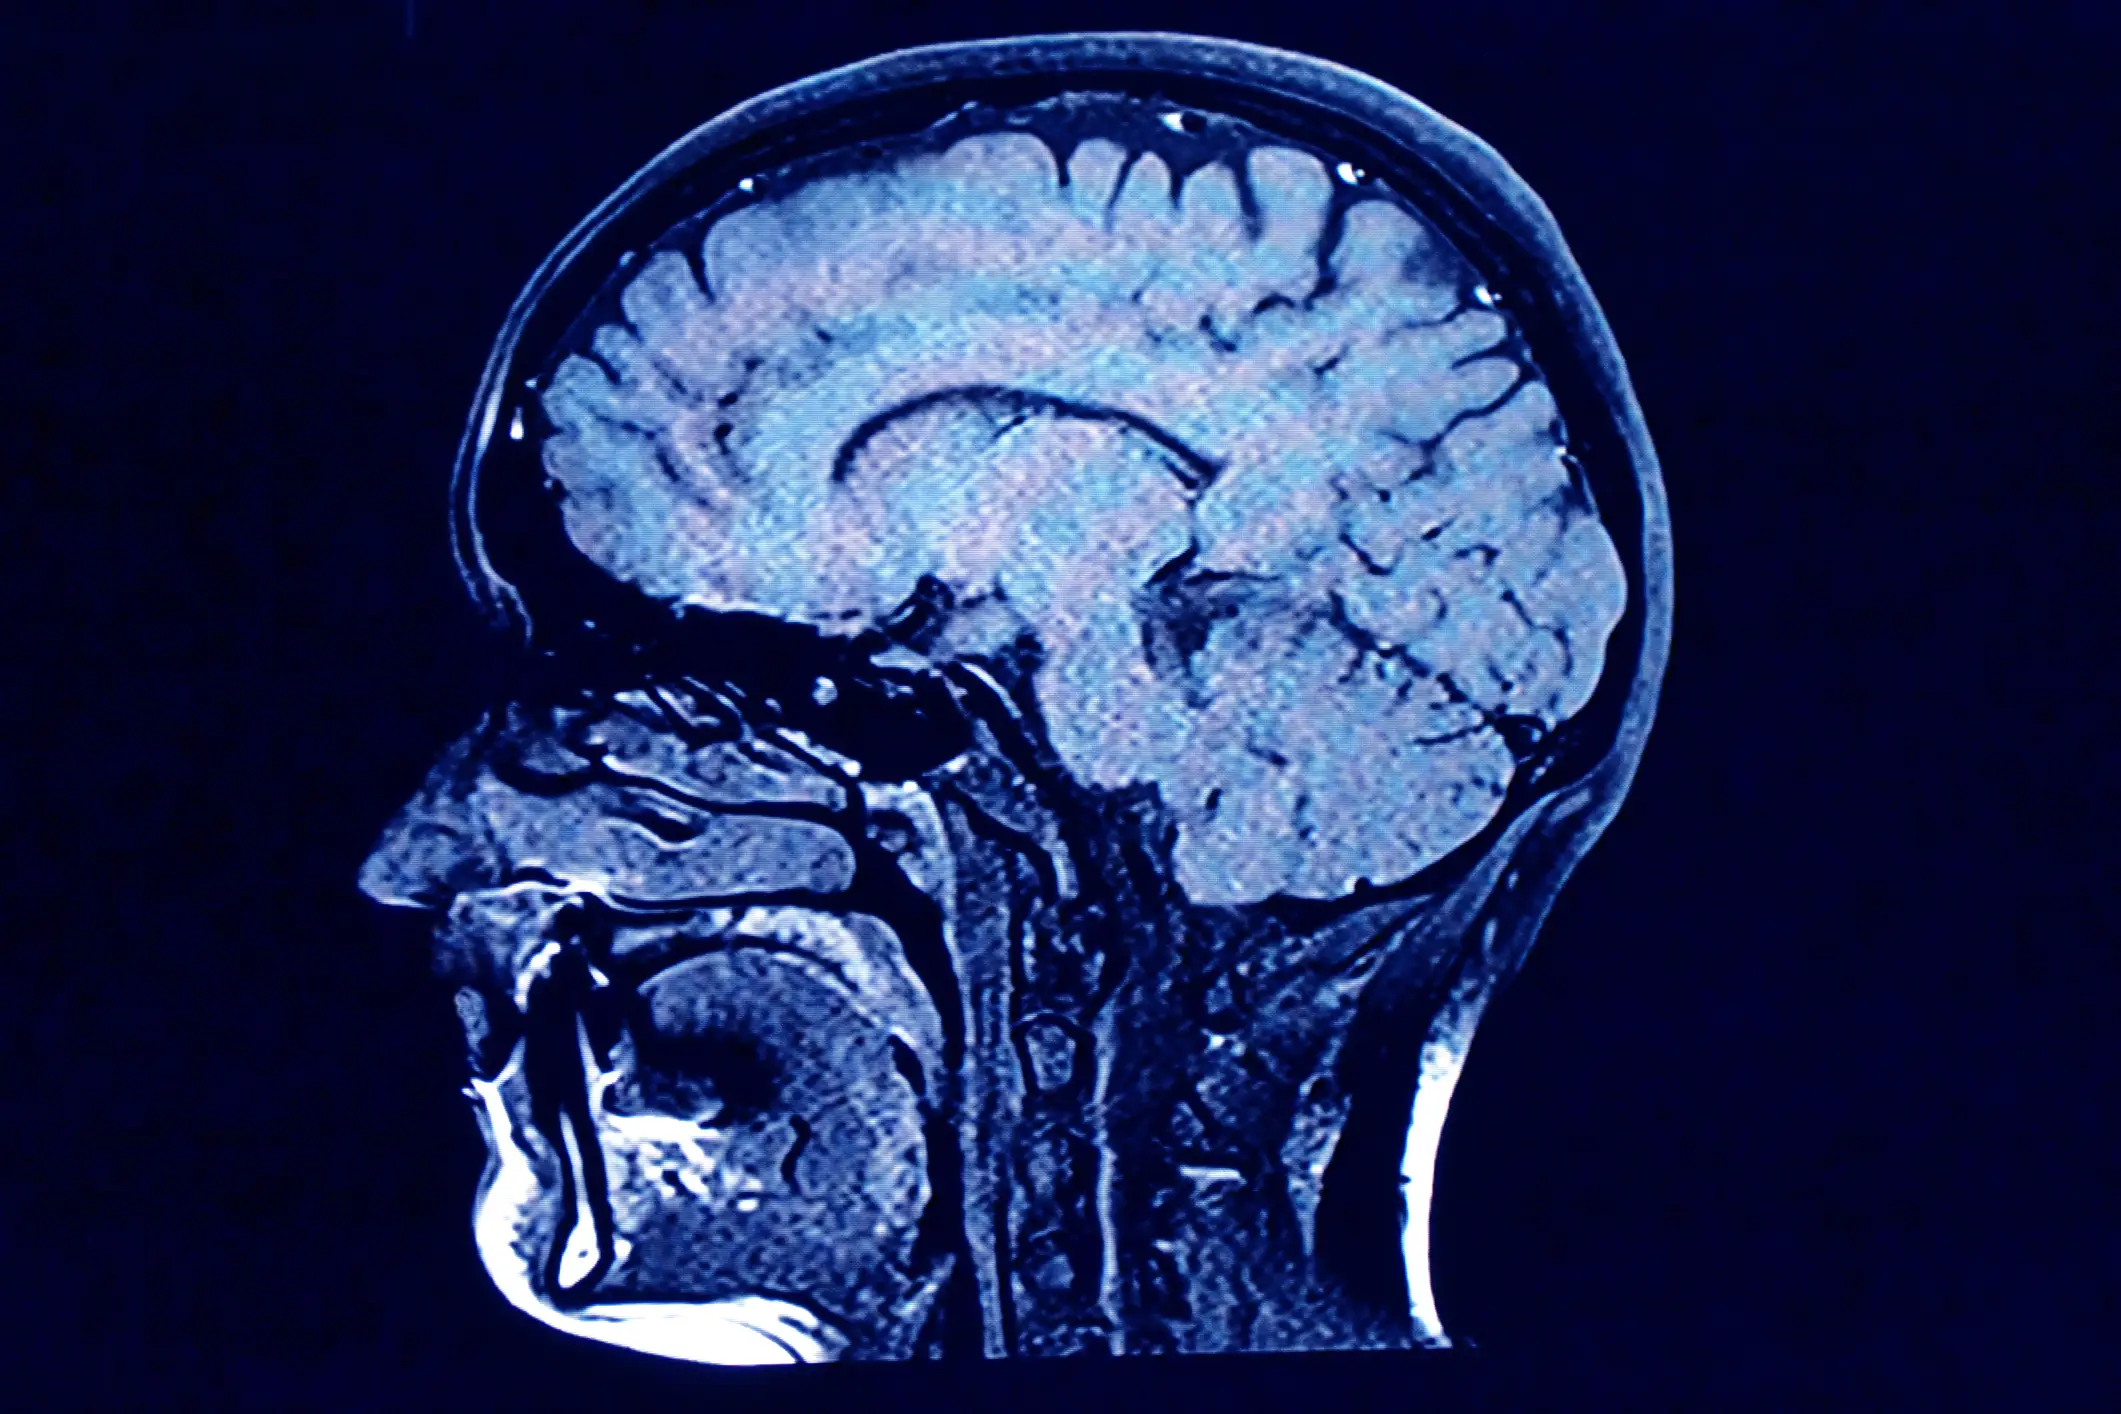

Scientists have taken a look at the effect dying has on the human brain and what they found is pretty insane.

The idea that your brain just stops working when you die couldn't be further from the truth, according to a 2022 study published in Frontiers in Aging Neuroscience.

A group of neuroscientists from the University of Tartu, Estonia ended up taking a deep dive into the brain of a patient who suffered with epilepsy.

Dr Raul Vicente and his team initially used continuous electroencephalography (EEG) to treat the patient, and to try to detect the seizures before they happened.

Despite the tragic incident, the scientists went and looked at a dying brain for, supposedly, the first time ever.

“We measured 900 seconds of brain activity around the time of death and set a specific focus to investigate what happened in the 30 seconds before and after the heart stopped beating,” said Dr Ajmal Zemmar, a neurosurgeon at the University of Louisville, US, who organised the study.

“Just before and after the heart stopped working, we saw changes in a specific band of neural oscillations, so-called gamma oscillations, but also in others such as delta, theta, alpha, and beta oscillations.”

They were able to confirm that the rhythmic brain wave patterns at the time of death were similar to the wave patterns when dreaming, memory recall, and meditation.

It gave a possible explication for why people often have vivid life recall in near-death experiences.

The age old saying of 'life flashing before your eyes' might have some truth in it.

So, there are different types of brain oscillations (brain waves), defined as patterns of rhythmic brain activity present in living human brains.

Gamma oscillations, for example, are present when concentrating, dreaming, and in memory and information.

“Through generating oscillations involved in memory retrieval, the brain may be playing a last recall of important life events just before we die, similar to the ones reported in near-death experiences,” Zemmar added.

“These findings challenge our understanding of when exactly life ends and generate important subsequent questions, such as those related to the timing of organ donation.

“As a neurosurgeon, I deal with loss at times.

“It is indescribably difficult to deliver the news of death to distraught family members.

“Something we may learn from this research is: although our loved ones have their eyes closed and are ready to leave us to rest, their brains may be replaying some of the nicest moments they experienced in their lives.”